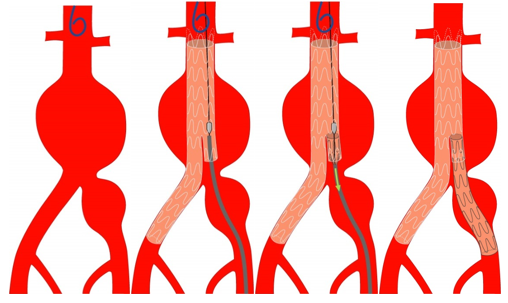

Im Jahre 1991 wurde von J.C. Parodi und N. Volodos ein neues Verfahren zur endovaskulären Ausschaltung von Aortenaneurysmen vorgestellt. Hierbei wird ein Stentgraft (mit Stoff ummanteltes Drahtgerüst) über die Leistenarterie operativ eingeführt, unterhalb der Nierenarterien platziert und freigesetzt. Das Blut fließt dann nicht mehr im Aneurysma sondern in dem Stentgraft und das Risiko der Ruptur ist damit ausgeschaltet. Voraussetzungen für die Anwendung dieses Verfahrens sind:

- ein ausreichender Abstand zwischen Nierenarterie und Beginn des Aneurysmas

- Ausreichend weite Beckenschlagadern (> 8 mm Durchmesser)

- Keine starken Knickbildungen

- Keine Nierenerkrankungen (Kontrastmittelgabe)